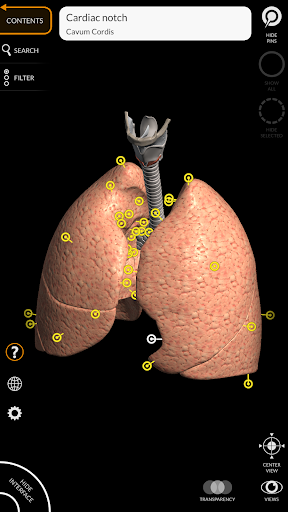

"Anatomy 3D Atlas" дозволяє легко та інтерактивно вивчати анатомію людини.

Завдяки простому та інтуїтивно зрозумілому інтерфейсу можна спостерігати кожну анатомічну структуру під будь-яким кутом.

Анатомічні 3D-моделі особливо деталізовані та мають текстури з роздільною здатністю до 4k.

АНАТОМІЧНІ 3D МОДЕЛІ

• Дихальна система